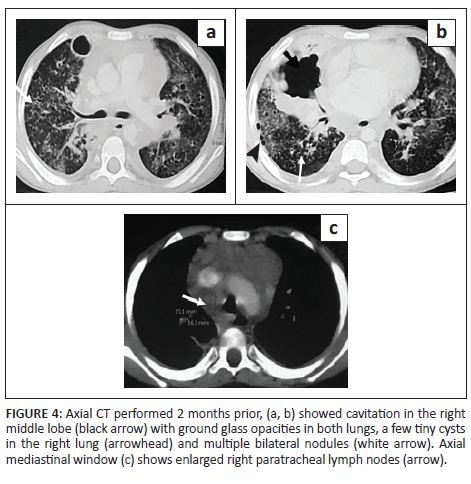

A 7-year-old boy, previously diagnosed with disseminated TB, on ATT for 3 months and on home oxygen therapy, presented to the paediatric outpatient department with complaints of intermittent increased cough from before and was found to have decreased oxygen saturation on room air. He underwent a CXR (Figure 3) that revealed a left loculated pneumothorax. The patient was admitted for assessment of multidrug resistant (MDR) TB and air leak. Contrast-enhanced CT chest (Figure 3) confirmed the left pneumothorax and revealed a thick-walled cavity in the right middle lobe and multiple cysts in both lungs. A previous CECT chest 2 months prior (Figure 4) was reviewed and revealed GGOs, a few tiny cysts, multiple bilateral nodules, along with necrotic mediastinal and abdominal lymphadenopathy, and a few small hypodense lesions in the liver suggestive of non-calcified granulomas. There was an interval increase in the number and size of the lung cysts, with a decrease in the number of nodules. Sputum microscopy and culture were negative. Bronchoscopy indicated signs of chronic inflammation and destruction of the distal bronchial segments and provided abnormal early entry into numerous cavitary structures, unlike the non-diseased areas where the distal branches gradually became smaller in size and did not allow entry into the lung parenchyma. Bronchial washings sent for culture were positive for TB (rifampicin sensitive). The patient was continued on ATT and demonstrated subsequent improvement.

Most patients with tuberculosis who develop lung cysts have extensive bilateral infiltrative and exudative disease as a result of the pneumonic process.1,4,7 All the described cases had disseminated TB (with involvement of two or more noncontiguous sites), along with diffuse, bilateral lung involvement. These cystic lung lesions are often associated with centrilobular nodules and branching opacities in surrounding areas.2,3,6 Antibiotics were administered in all five cases, and none showed superadded bacterial infection. Three cases revealed numerous nodules, GGOs and consolidations. In Case 2, two CT studies were performed 2 months apart, which demonstrated a reduction in the lung nodules on treatment, with a corresponding increase in the number of cysts. Two cases showed predominantly cystic changes, with only a few nodules. One of these (Case 5) had received 5 months of ATT for MDR TB. In the presented cases, the cystic lesions developed during isoniazid treatment, rather than before or after treatment. This is in contrast to previous literature that describes certain instances of patients developing cystic lung lesions after isoniazid treatment.7